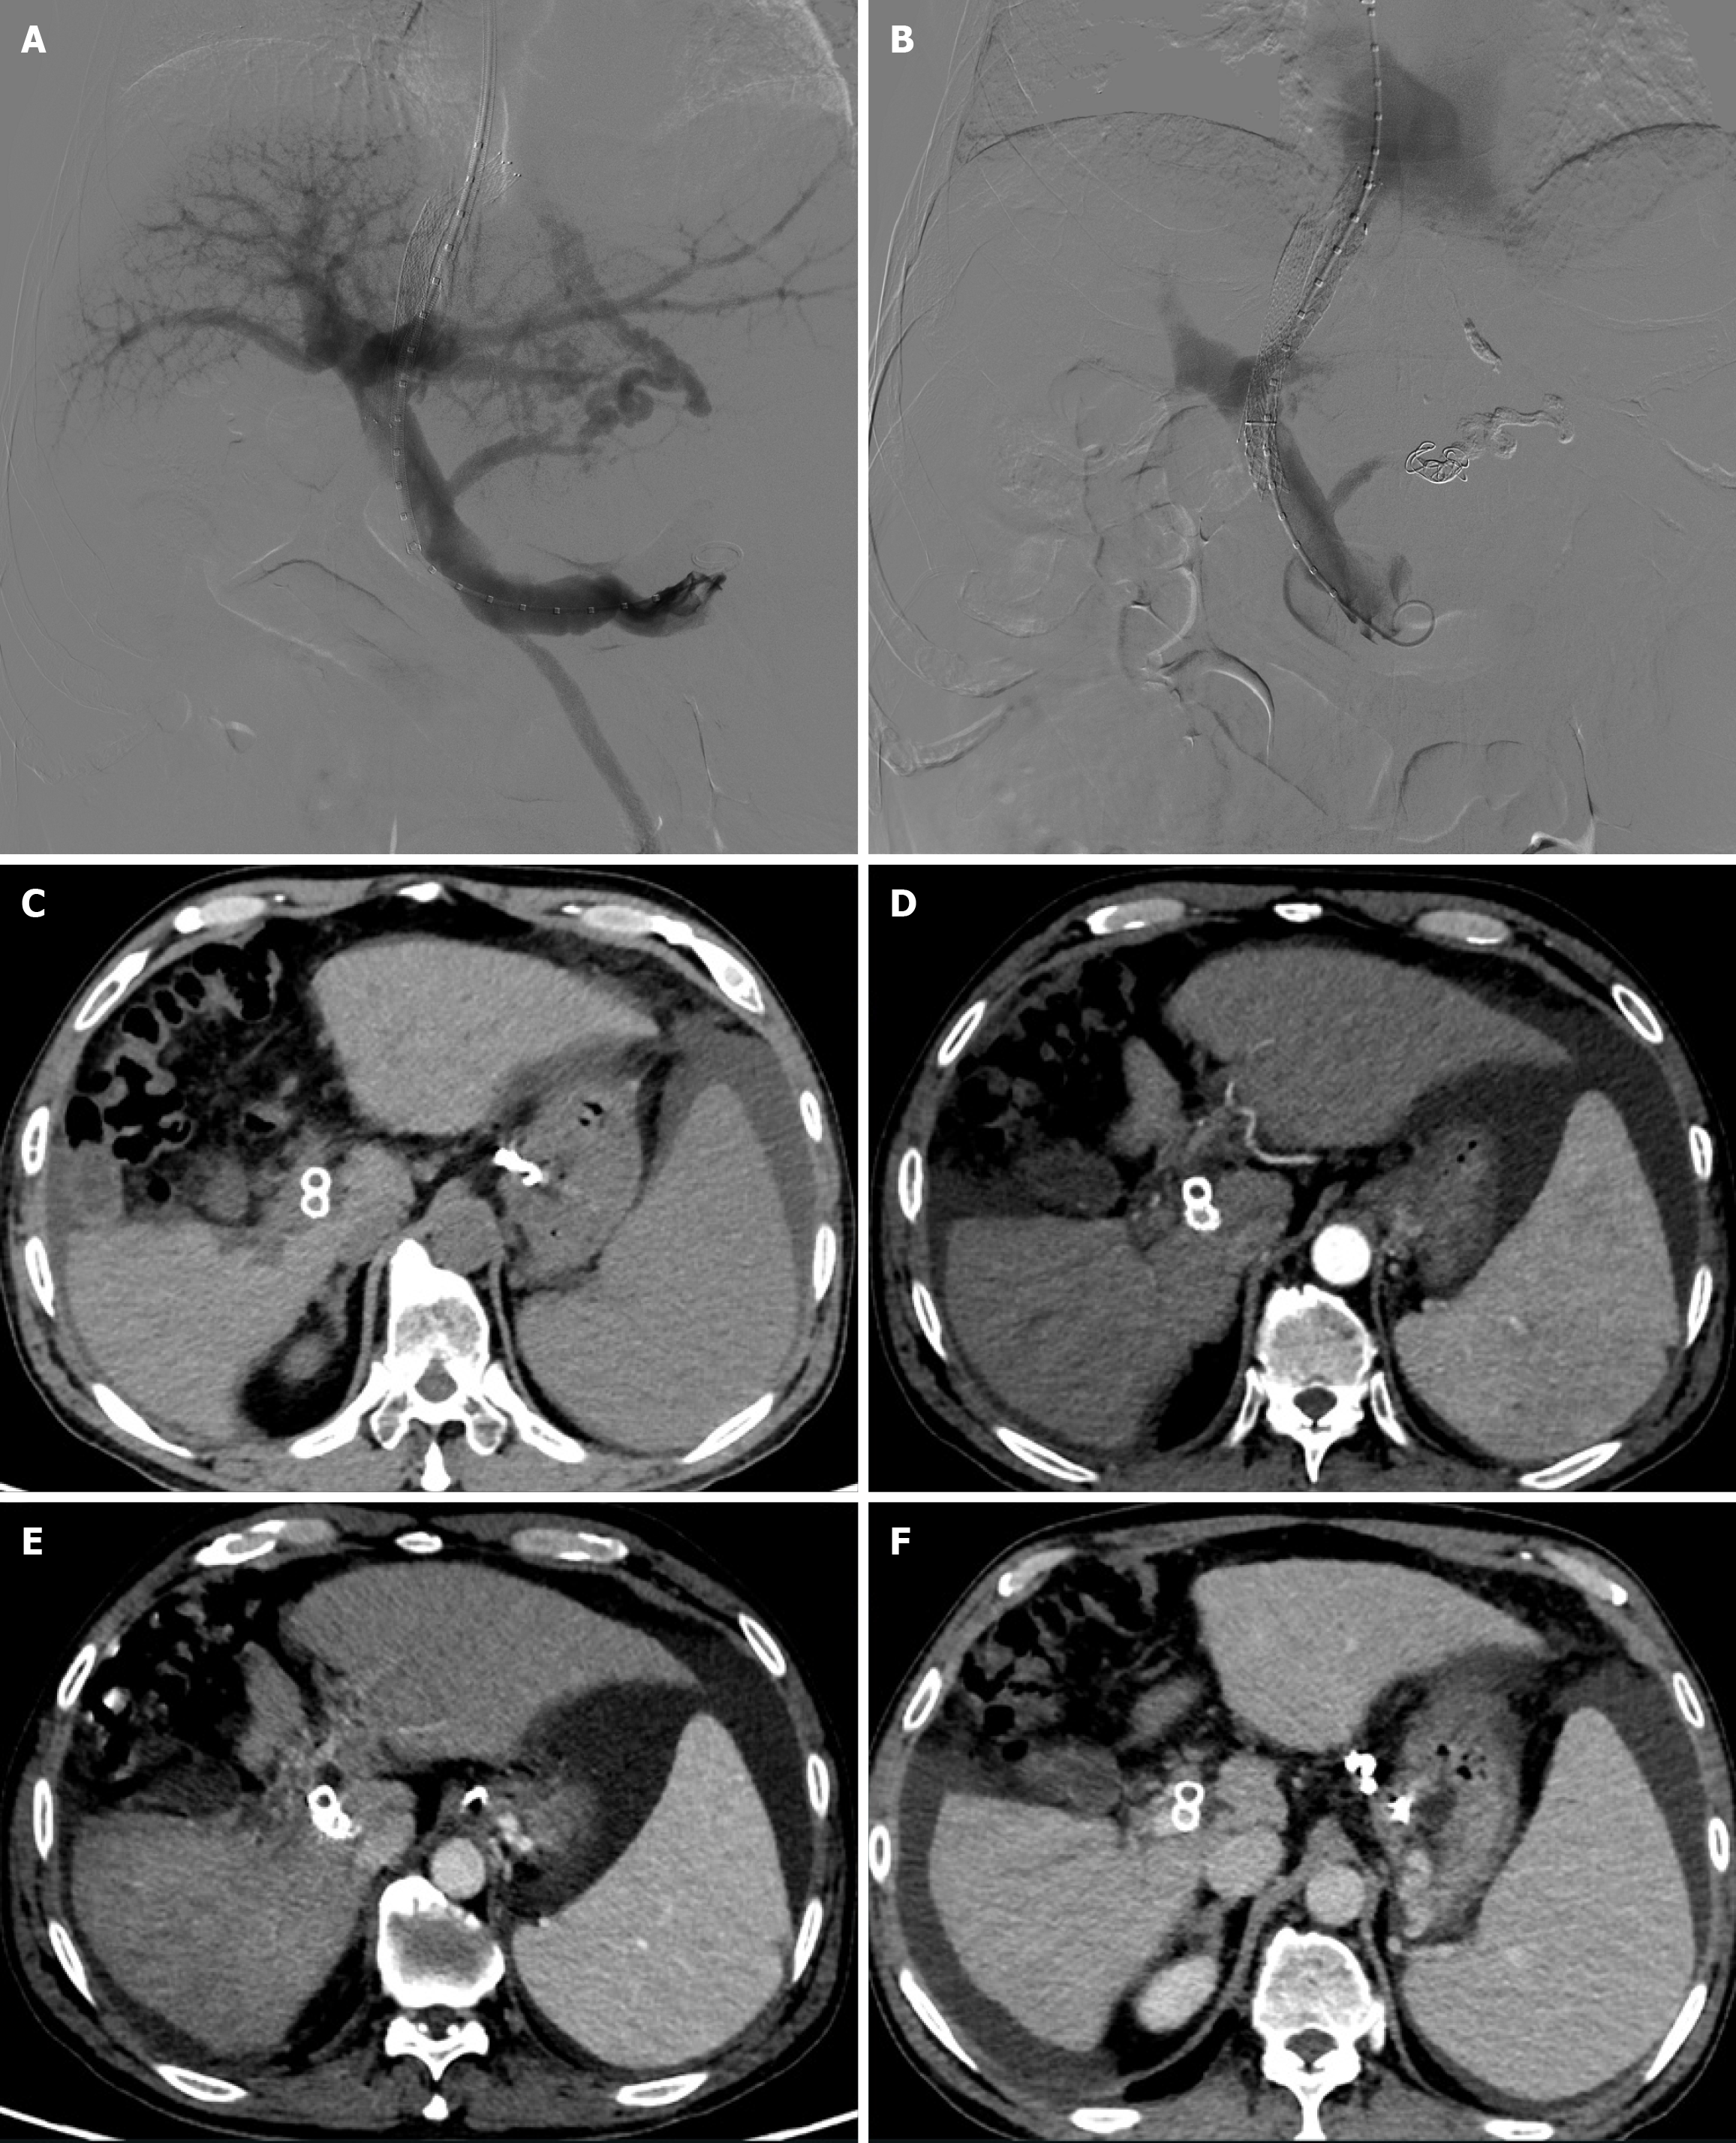

A TIPS was created with a bare metal stent/stent-graft combination as the Viator stent was not covered by National Health Insurance at that time, although it is available in China. First, a TIPS was created with an 8 mm × 80 mm self-expanding bare Nitinol stent (Epic Vascular Stent: Boston Scientific, United States) from the right hepatic vein to the left portal vein. Subsequently, an 8 mm × 50 mm Viabahn stent-graft (WL Gore Associates, Inc., Flagstaff, AZ, United States) was placed to cover the entire intraparenchymal portion of the shunt tract. The distal portion of the bare metal stent overlapped the stent-graft, while its proximal portion of approximately 25 mm protruded into the inferior vena cava (IVC) (Figure 3A). The final portography demonstrated a patent shunt (Figure 3A). Portal pressure decreased from 35 to 25 mmHg, and portocaval pressure gradient (PPG) decreased from 25 to 11 mmHg.

Following the procedure, melena disappeared immediately and the patient was transferred out on day 3. And the patient was advised to undergo follow-up liver CT angiography at 1 and 3 months postoperatively to assess shunt patency and monitor for the development of hepatocellular carcinoma. Subsequent evaluations should then be performed every six months thereafter. CT images one month after TIPS creation revealed metallic continuity of the stents (Figure 3B). However, follow-up CT imaging at 15 months post-procedure demonstrated stent fracture at the hepatocaval confluence (Figure 3C), although notably, the stent lumen remained patent (Figure 3D). A 20 mm stent fragment was radiologically confirmed to be lodged within the infra-diaphragmatic segment of the IVC, exhibiting positional stability without evidence of proximal migration toward the right atrium on serial imaging surveillance. The patient was treated conservatively as he was asymptomatic. CT images and color Doppler ultrasound 14 months after the procedure demonstrated neither further stent fracture nor further dislocation of the stent fragment. No symptoms associated with the stent fracture were observed for 15 months. However, the patient was readmitted 30 months post-TIPS due to recurrent esophagogastric variceal bleeding and ascites. Enhanced abdominal CT indicated occlusion of the original shunt (Figure 4). An attempt to revise the dysfunctional shunt via a stent-in-stent approach was conducted but was unsuccessful. Con